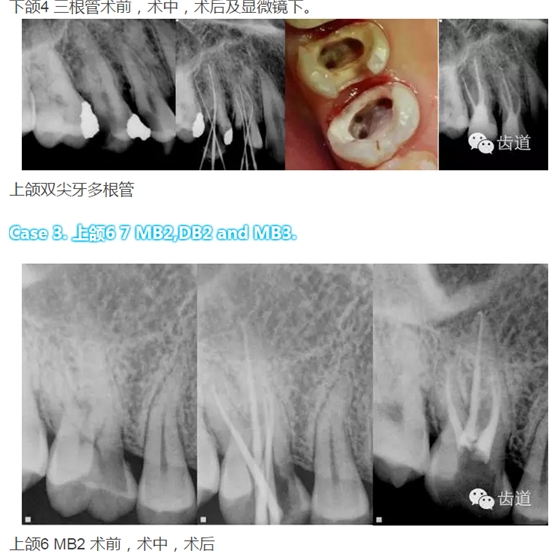

下頜第一磨牙:為3-4個根管,遠中雙根管的發(fā)生率為51.4% 左右,側(cè)支根管發(fā)生率為30%左右;

下頜第二磨牙:多為3個根管,C型根管發(fā)生率約為31.5%。